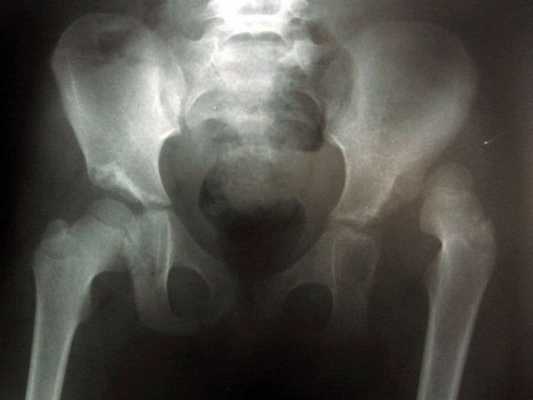

Инструментальные исследования: на рентгенограммах тазобедренных суставов при подвывихах отмечается смещение головки бедра латерально, часть головки остается непокрытой крышей, линия Шентона нарушена, головка деформирована, скошенность крыши вертлужной впадины.

При вывихах головка бедра смещена вверх до крыла подвздошной кости, находится во вновь образованной впадине, расположенной проксимально от первоначальной впадины.